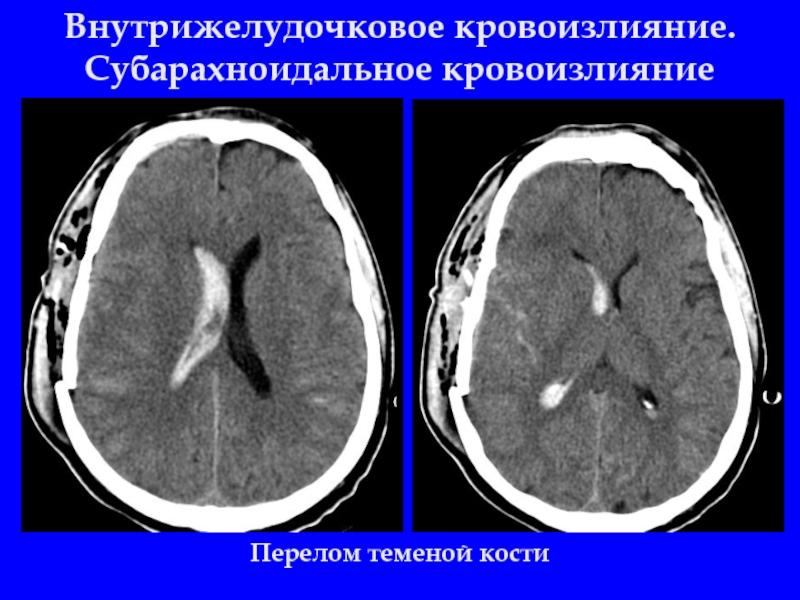

Слайд 28Внутрижелудочковое кровоизлияние. Субарахноидальное кровоизлияние

Перелом теменой кости